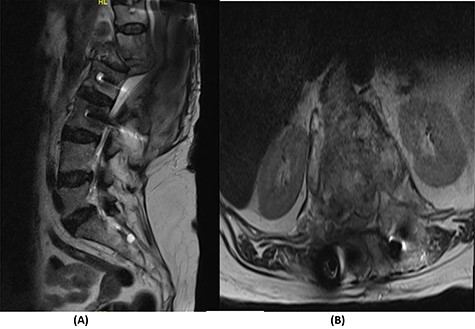

Fourteen months later, the patient presented to the ED complaining of generalized body pain associated with malaise. The neurological examination was unremarkable. An MRI of the lumbar spine showed recurrence of the lesion with loosening and pullout of the implant, kyphosis and dislocation, with cord compression and collection (Fig. 2). Computed tomography (CT) scan showed a burst fracture of the L1 vertebra with loose screws (Fig. 3). CRP was 21 mg/l, ESR was 115 mm/h and procalcitonin was 0.051 ng/ml. The decision was made to do a CT-guided biopsy from the left paraspinal mass of T12–L1. The tissue biopsy was subjected to TB-polymerase chain reaction testing and acid-fast bacillus culture; both results were positive for M. tuberculosis. The patient was diagnosed with TB spondylitis and was started on the full anti-TB four-drug regimen.

(A) T2-weighted sagittal spine MRI demonstrating changes at the thoracolumbar spine with previous decompression for pathological fracture of L1 vertebra. There is interval progression of the disease with a soft tissue mass at the previous site extending to the prevertebral and epidural spaces, compressing the neural element. (B) T2-weighted axial spine MRI of the corresponding level of L1 vertebral body.